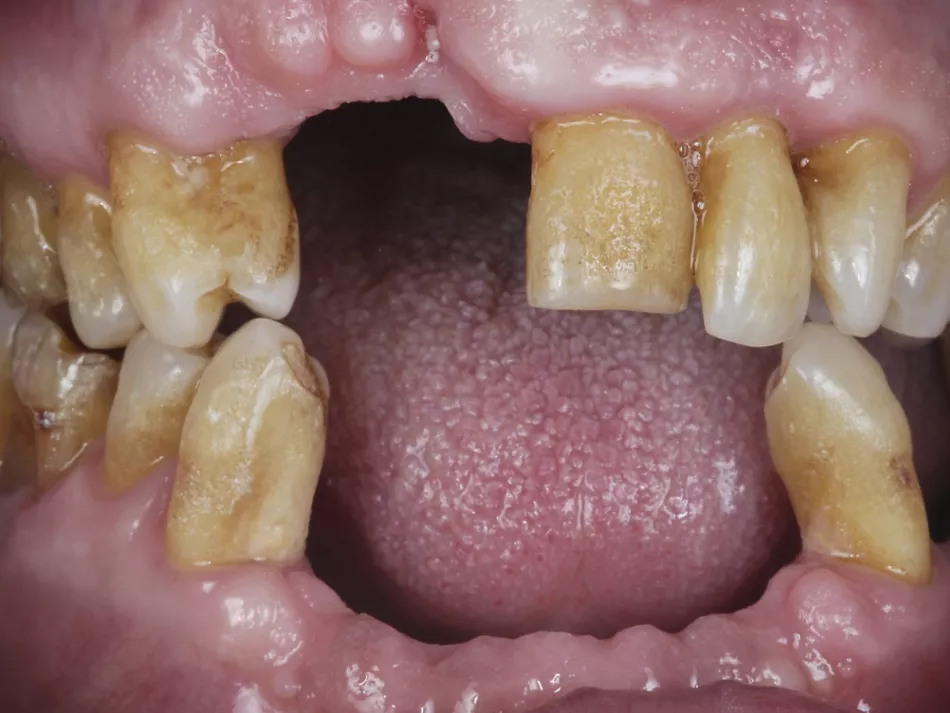

2. Preoperative frontal view showing several missing teeth in both jaws incisor/canine/premolar regions, gingival recession and atrophied alveolar ridges

and remaining carious teeth.